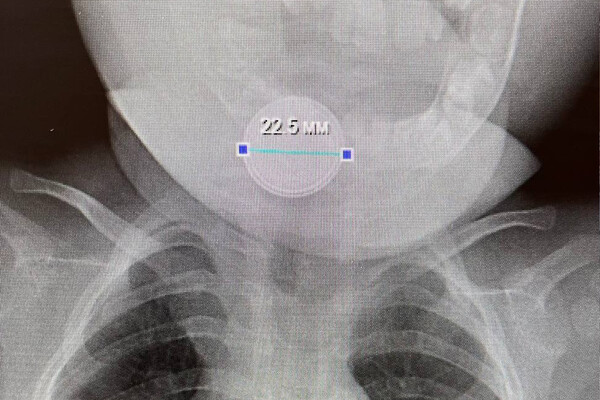

В приемное отделение больницы села Казанское был доставлен десятиместный младенец, ребенок с трудом дышал, сильно кашлял и вел себя беспокойно. В ходе обследования медики обнаружили в желудке маленького пациента инородное тело — круглую батарейку.